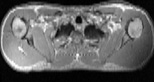

Visible Human male: Sectio transversalis 1310

CT

NMR

Pd T1 T2